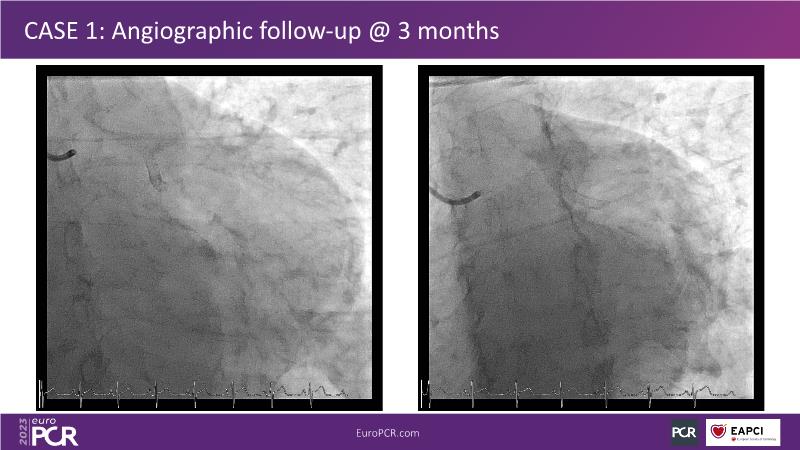

• To understand why you can count on customised drug delivery platform of DES+DCB in complex settings with imaging-based evidence through case presentations

• To gain an insight on how the next generation no-polymer DES+DCB stent platform will address the unmet needs in coronary artery disease patients